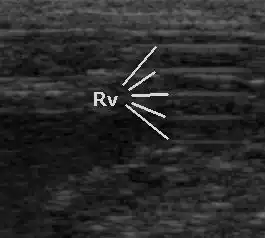

Ungenügende Ankopplung des Schallkopfes an die Hautoberfläche verursacht das Auftreten mehrerer Echos im gleichen Abstand, ohne dass ein auswertbares Bild entsteht (Reverberationen).